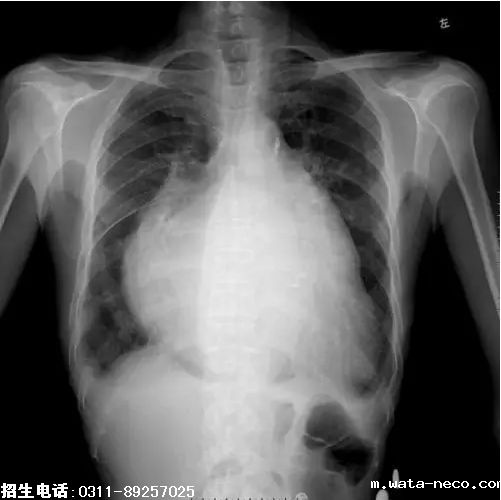

8、题干:女,65岁。劳力性呼吸困难进行性加重5天。结合X线片,此诊断为

A、正常胸片

B、主动脉型心

C、二尖瓣型心

D、普大型心

E、胸腔积液

答案:D

解析:由X线可知,该患者心影普遍增大,心室和心房均有明显的扩张,为普大型心。(D对)